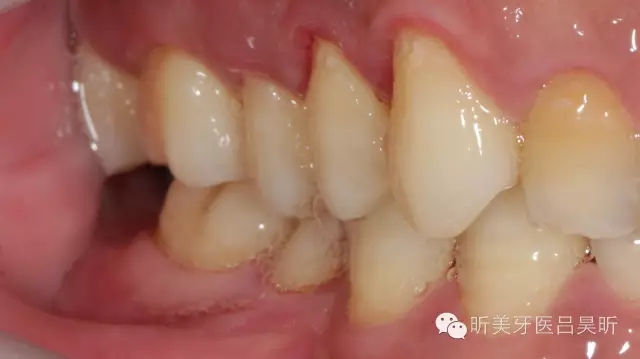

術(shù)前口內(nèi)檢查,可見(jiàn)牙槽骨寬度良好,角化齦量適中

可見(jiàn)種植位點(diǎn)舌側(cè)區(qū)凹陷,牙槽骨上部舌傾明顯。